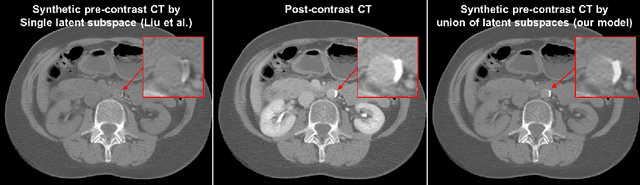

Abstract:Calcified plaque in the aorta and pelvic arteries is associated with coronary artery calcification and is a strong predictor of heart attack. Current calcified plaque detection models show poor generalizability to different domains (ie. pre-contrast vs. post-contrast CT scans). Many recent works have shown how cross domain object detection can be improved using an image translation model which translates between domains using a single shared latent space. However, while current image translation models do a good job preserving global/intermediate level structures they often have trouble preserving tiny structures. In medical imaging applications, preserving small structures is important since these structures can carry information which is highly relevant for disease diagnosis. Recent works on image reconstruction show that complex real-world images are better reconstructed using a union of subspaces approach. Since small image patches are used to train the image translation model, it makes sense to enforce that each patch be represented by a linear combination of subspaces which may correspond to the different parts of the body present in that patch. Motivated by this, we propose an image translation network using a shared union of subspaces constraint and show our approach preserves subtle structures (plaques) better than the conventional method. We further applied our method to a cross domain plaque detection task and show significant improvement compared to the state-of-the art method.